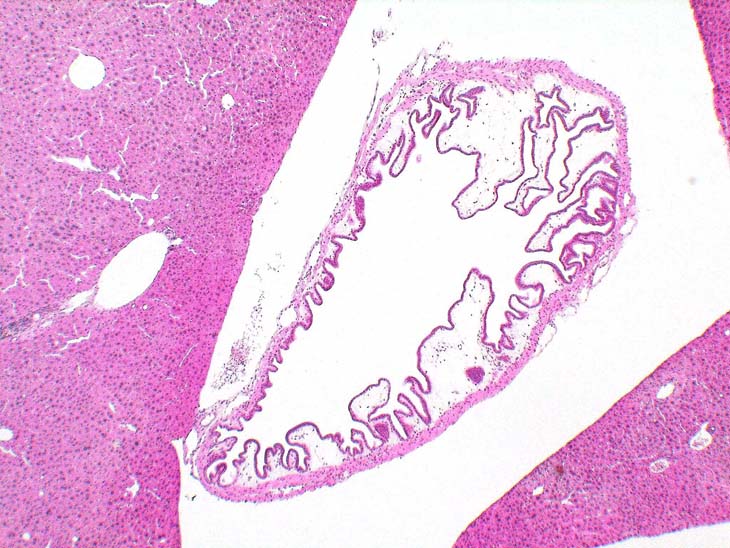

Gallbladder, submucosal edema. This change represents a sporadic finding in mice.